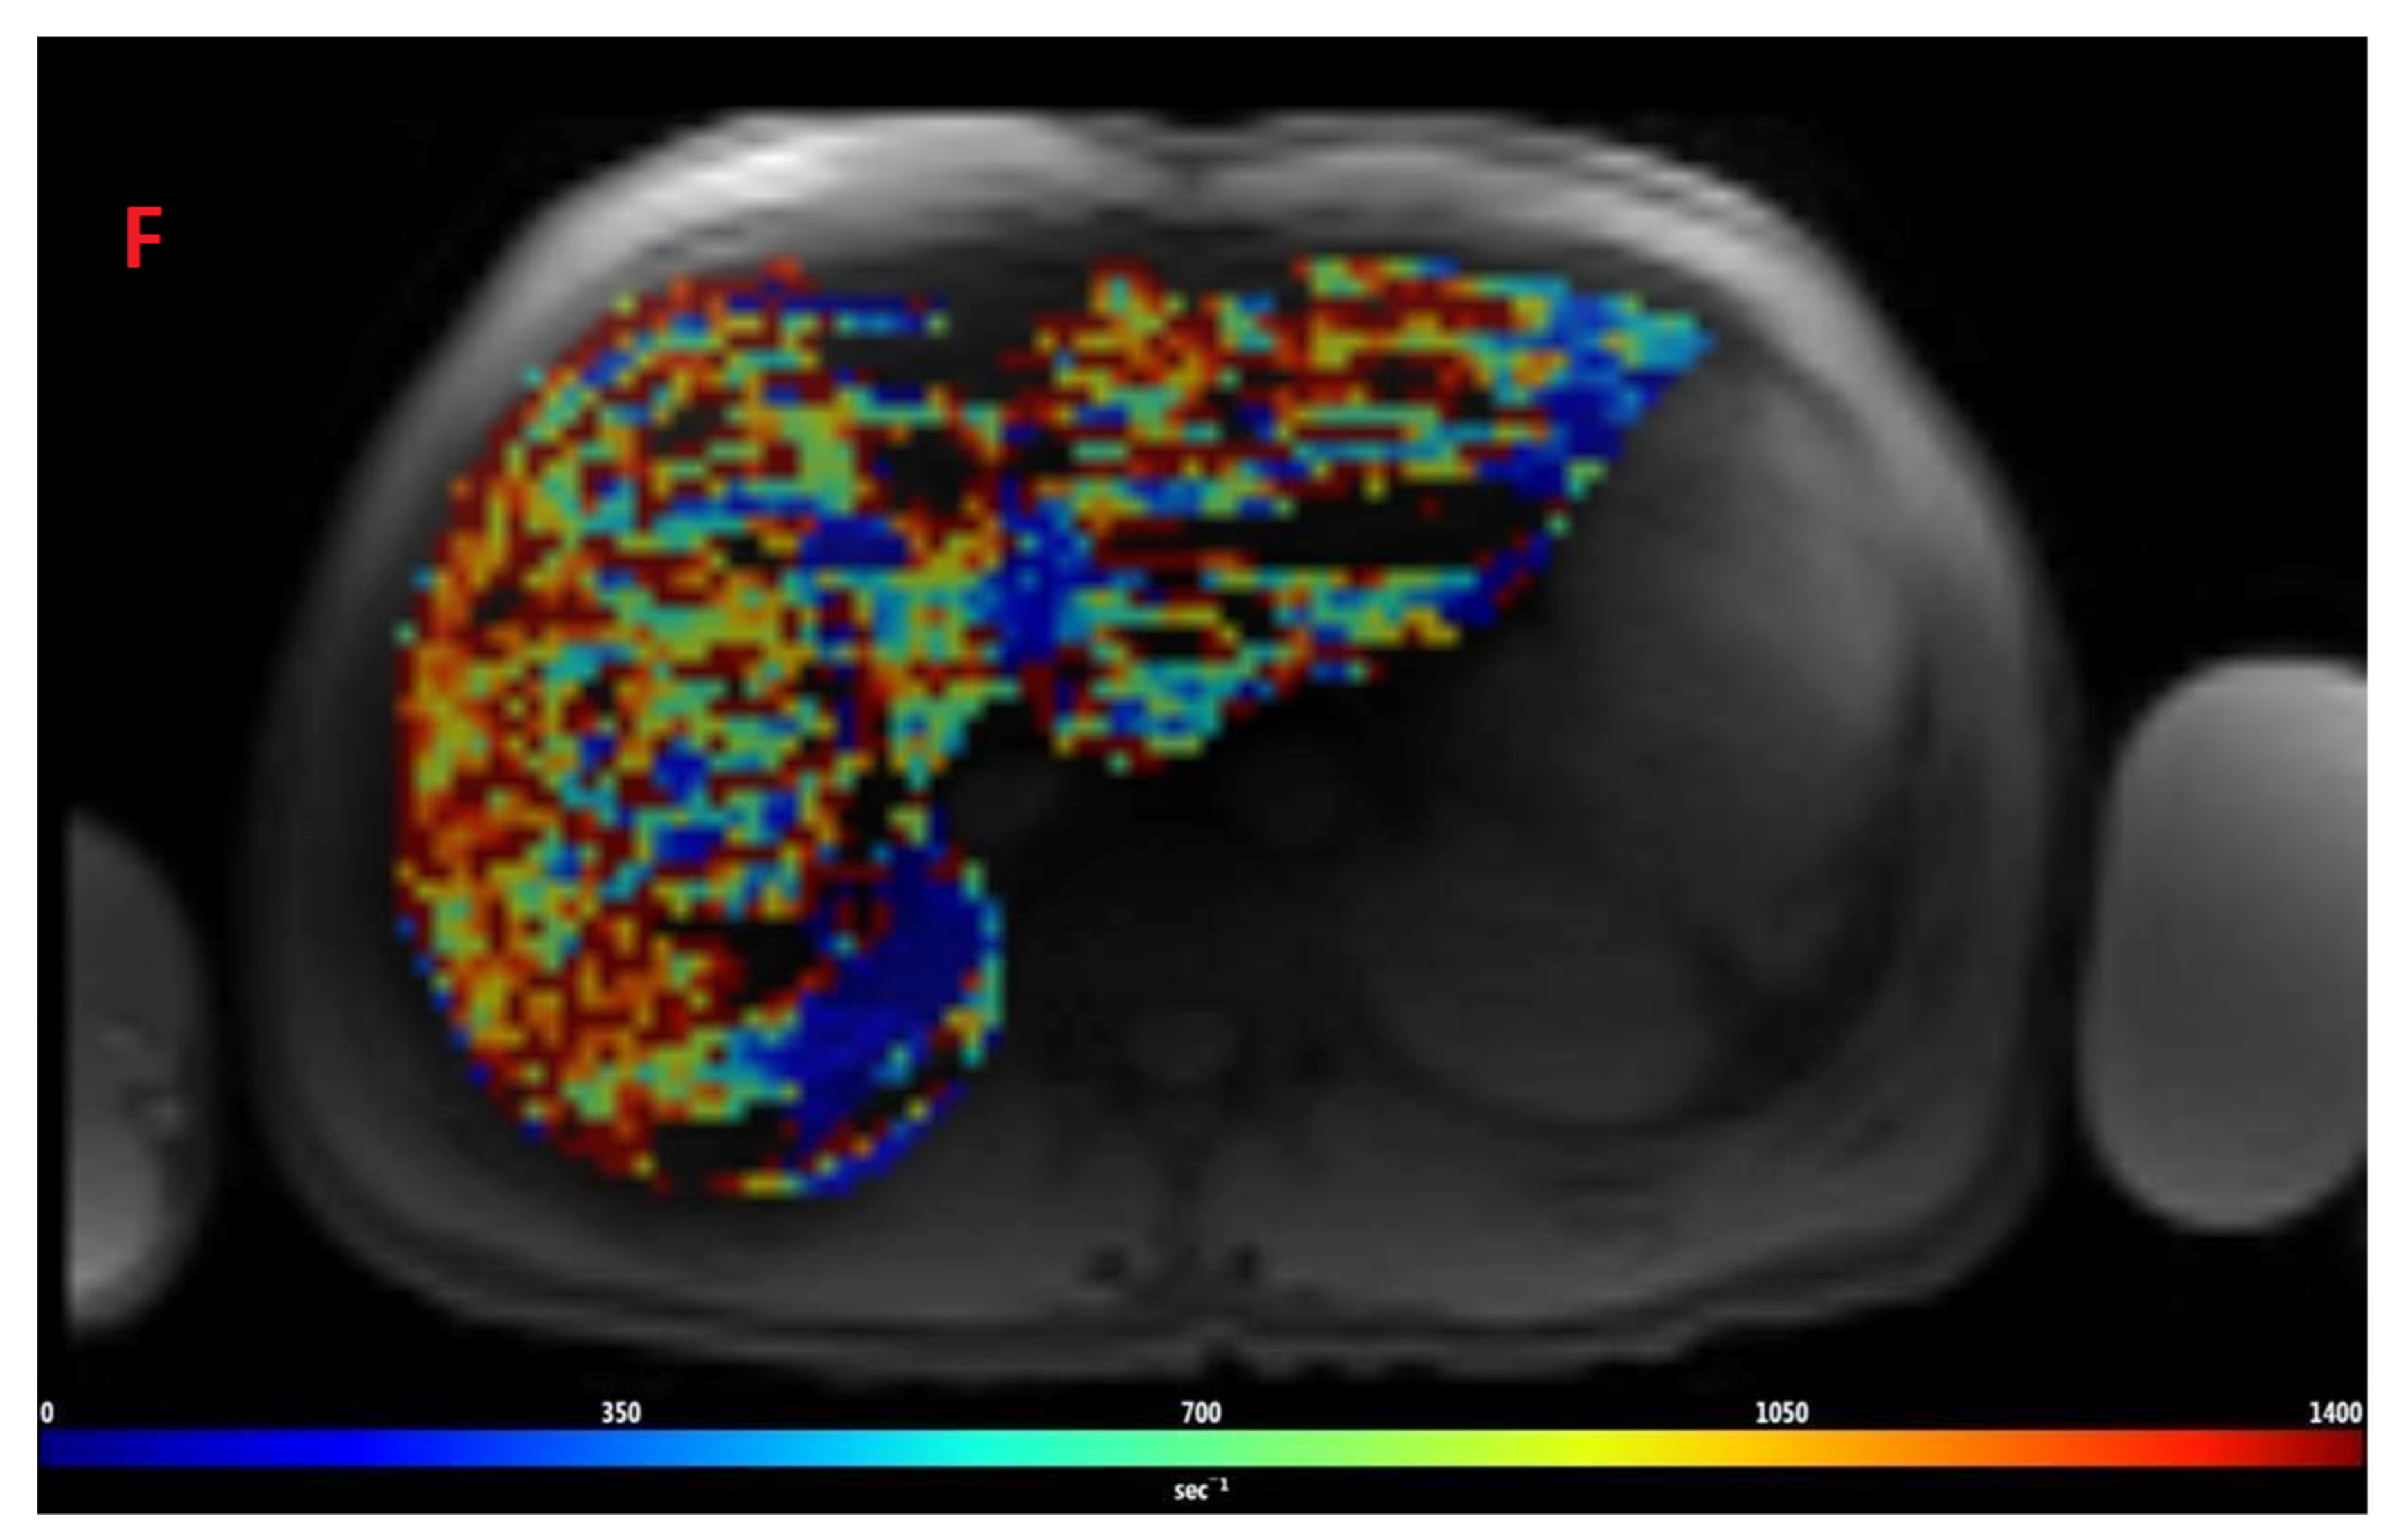

The mean value of LIC R2* at the first scan of the subjects was 10.4 ± 7.9 mg/g (range: 1.35 mg/g to 39.1 mg/g), and the mean value of R2* during the last follow-up was 8.4 ± 6.4 mg/g (range: 0.4 mg/g to 31.1 mg/g). The average rate of change of LIC determined by R2* relaxometry (∆LIC R2*) was −0.0047 ± 0.012 mg/g per month. Representative images in a patient with beta thalassemia assessed for iron overload, which provided an estimated LIC of 26.6 mg/g at time point 1 and an estimated LIC of 31.1 mg/g at time point 2 two years later, are shown in Figure 2. T2* relaxation curves for the two time points are shown in Figure 3.

Figure 2.

Representative images showing (A) the gradient axial echo slices; (B) post-processed liver iron concentration (LIC) map (color scale shows the range of LIC from 0 to 45 mg/g); and (C) R2* map in a patient with beta thalassemia assessed for iron overload at time point 1, which provided an estimated LIC of 26.6 mg/g. The lower panel (D–F) demonstrates gradient axial echo slice, post-processed LIC map, and R2* map, respectively, acquired from a scan performed after two years. The estimated LIC was 31.1 mg/g at time point 2.